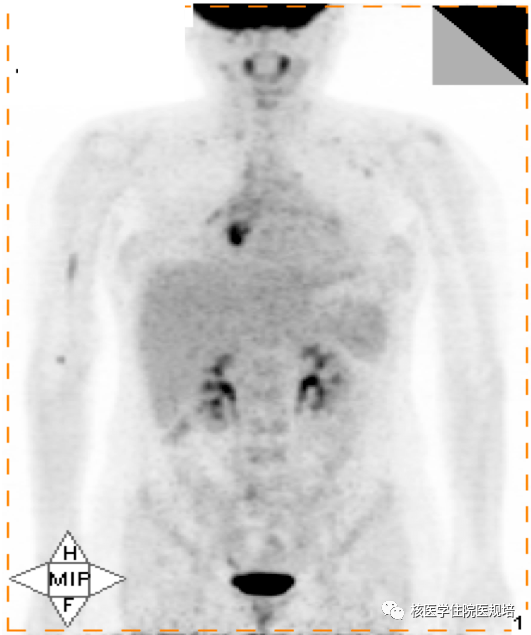

规培朋友看过来--核医学病例及解析(183号)

规培朋友看过来--核医学病例及解析(183号)